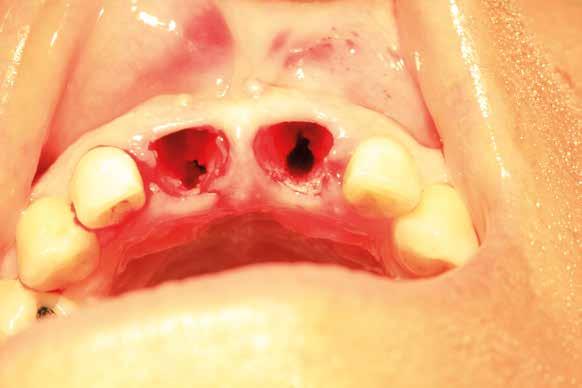

Estrazione di 3 elementi dentari complicata da frattura coronale di 2.4 e presenza di 2 corone protesiche unite su denti pluriradicolati. L’approccio deve prevedere la rimozione delle corone protesiche e la separazione delle radici, semplificando le manovre di estrazione e consentendo di risparmiare i tessuti molli pericoronali e prevenire la frattura

Il rispetto dei tessuti molli consente di ridurre i tempi di guarigione, sebbene a siti più ampi corrisponda un tempo di ripristino o maggiore. Il mantenimento delle corticali vestibolari, palatine e l’assenza di alveolite post-estrattiva riducono l’atrofia ossea.

L’esame CBCT ha rivelato un quantitativo di osseo sufficiente a procedere con l’intervento implantare, anche se erano ancora visibili le zone delle estrazioni; inoltre ha evidenziato una lesione osteolitica a carico del 3.5 che abbiamo dunque deciso di estrarre (Figg. 7-20).